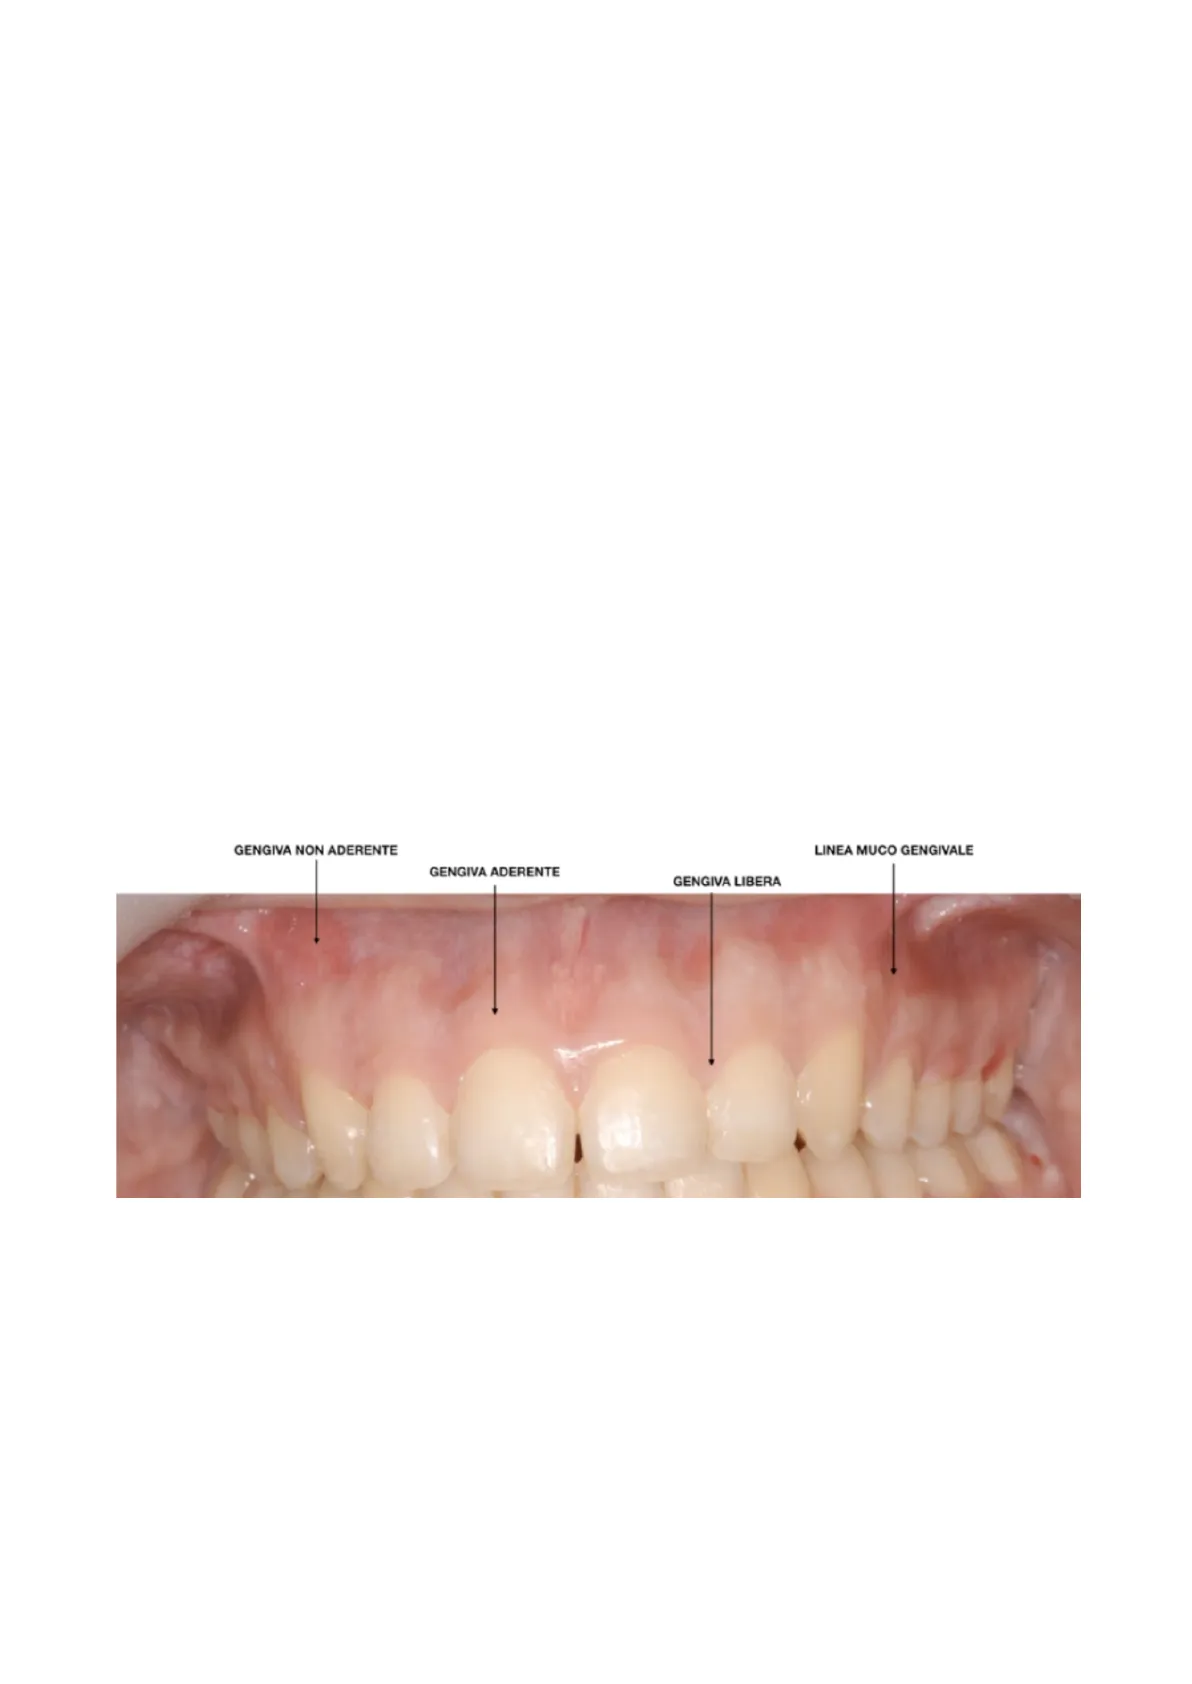

La gengiva si può distinguere in 3 componenti:

La linea che congiunge la gengiva aderente a quella non aderente si chiama linea muco-gengivale. La gengiva è unita al dente sottostante grazie a dei fasci di fibre.

GENGIVA NON ADERENTE LINEA MUCO GENGIVALE GENGIVA ADERENTE GENGIVA LIBERA